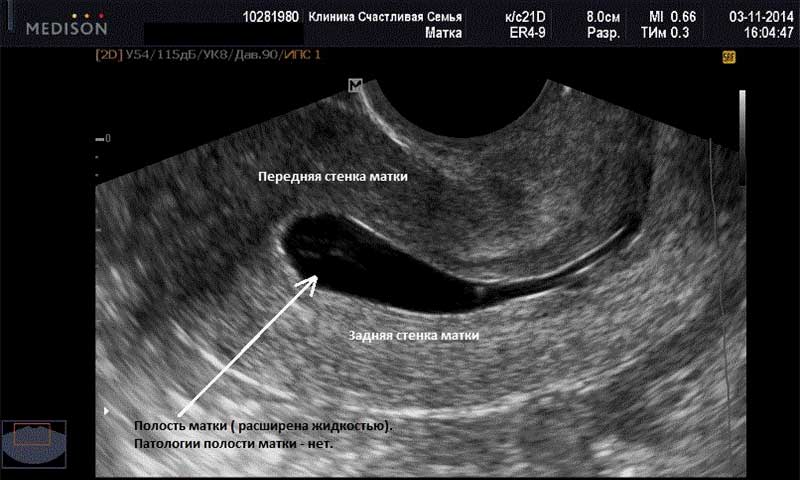

23ДПП первое УЗИ: 1ПЯ-средний внутренний диаметр-10мм, эмбрион четко не визуализируется, канал шейки матки закрыт, матка в нормотонусе. Заключение:Беременность соответсвует сроку 3 недели 2 дня (от зачатия)

Мое первое УЗИ на 19ДПП. В полости матки визуализируется 1ПЯ, СВД-5,5мм округлой формы. ПЯ и ЛЯ с множеством ж/тел. Диагноз — беременность малого срока. Теперь следующее УЗИ на 34ДПП, 25.08.10. Сказали, что должно сердечко биться на сл.УЗИ.

Привет девочки. Мне делали узи на 30ДПП и уже увидели эмбриончика и серцебиение, а размеров тоже не указано только написоно срок беременности 6-7 акушерских недель. Так что девочки неволнуйтесь раньше времени, сходите на узи еще раз через недельку и там будет все видно. А пока не нервничайте и детишек хватит нервировать.

Привет всем! Опять я вся такая нервная. С начала протокола прошло уже 6 недень. И вот я вся такая еле дотерпевшая прошла УЗИ. И теперь уже 2 дня не сплю. Результат: на 24 ДПП плодное яйцо 13 мм с эмбрионо КТР 3,3 мм (отвечает 5 неделям, желточный мешок 2.6 мм ЧСС 112 уд